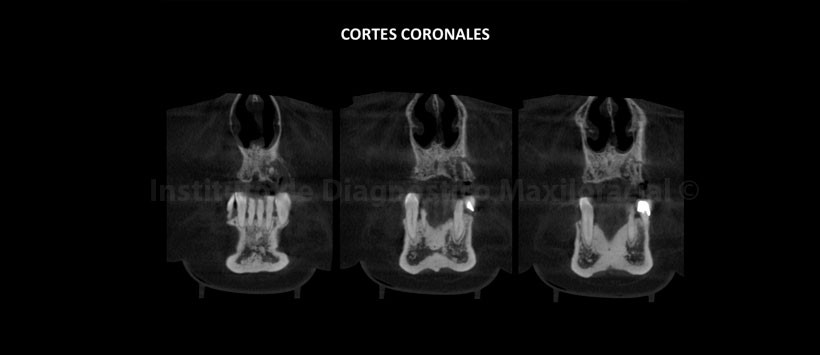

A la evaluación de la tomografía volumétrica (CBCT) en los cortes axiales (Figura 2, 3), coronales (Figura 4,5), transaxiales (Figura 6,7) y tangenciales (Figura 8), se aprecia proceso osteolítico de límites mal definidos, bordes difusos, localizado a nivel del maxilar superior del lado izquierdo, que se extiende en sentido mesio-distal desde la pieza 2.2 hacia los lechos alveolares de las piezas 2.3 y 2.4 y en sentido cefálico-caudal de la címa de reborde alveolar hasta el piso del seno maxilar a nivel de la zona de pieza 2.5. Se aprecia, presencia de secuestros óseos y reacción periostal en la tabla ósea vestibular y en zona del piso del seno maxilar.